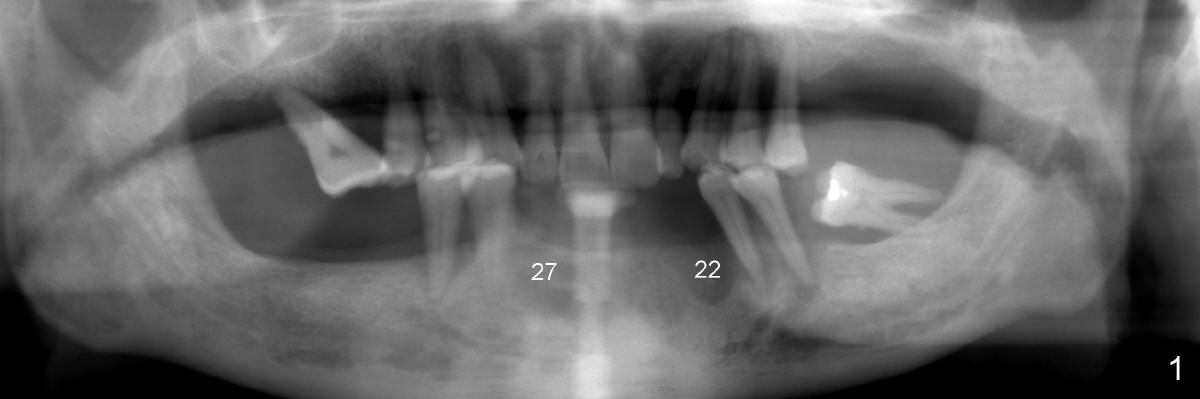

A 52-year-old man seeks treatment 2 months following loss of #22-27 fixed partial denture (FPD) (Fig.1,2). The remaining dentition has moderate to severe chronic periodontitis. Scaling & root planing has been done for the upper arch. Full mouth reconstruction is planned for the lower one in two steps. In the first procedure, the teeth #18, 20 and 21 are extracted; an incision is made from #20 to #27; two immediate implants are placed at the sites of #20,21 (one or two piece, Fig.3,5 X); another two implants at #22,27 (recently healed sites: Fig.3-5: I) and two one piece implants at lateral incisor region (I: for an implant supported FPD). In case one of the lower left premolars cannot have an implant due to proximity to the nerve, a FPD can be fabricated in the canine/premolar sextant. A splinted immediate provisional restoration will be fabricated from #20-27 immediately.